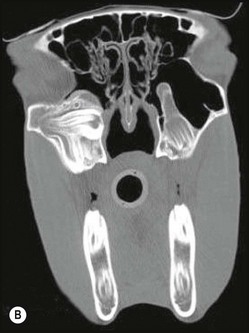

image image image

Fig. 13.43 Radiograph (A) and CT images (B and C) of a compound odontoma in a 2-year-old TB colt.

(Images courtesy of J. Easley.)